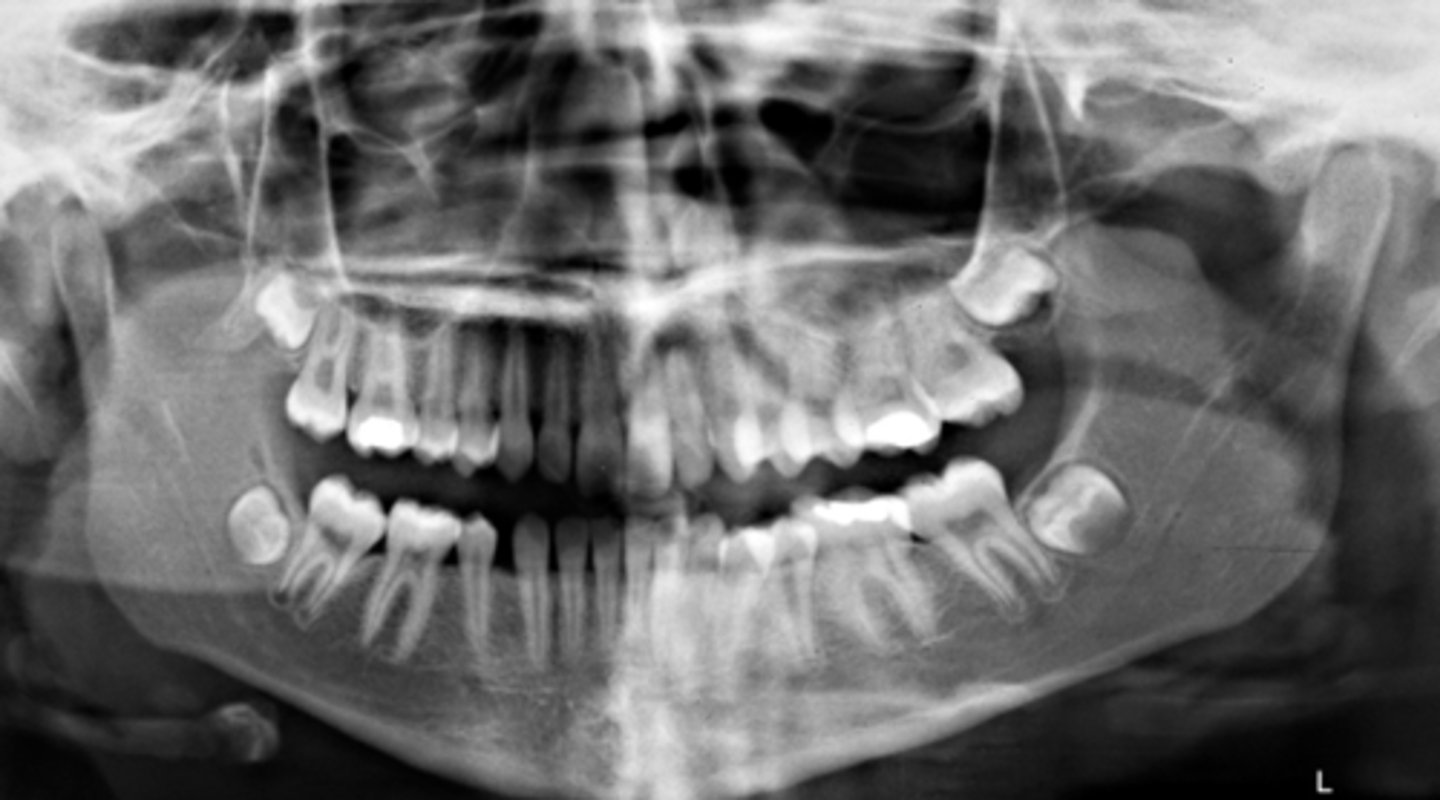

- patient didn't close all the way

- chin was down

- patient is too close to the film/receptor

What are the problems in this panoramic image?

A) mid-sagittal

What light needs to repositioned to fix this image?

B) Frankfort plane

C) focal trough

What light needs to be repositioned to fix this image?